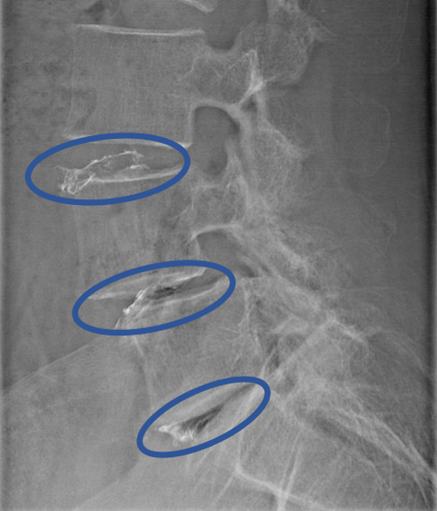

DiscoGelを入れた後の画像になります。

治療は 30分程度で終了

回復室で休憩後、歩いて帰院されました。